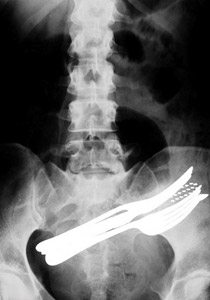

أدوات طعام في جوف مريض!! |

ورغم أن الصور ممعنة في الغرابة ومذهلة للغاية إلا أنها تأتي بلا تفسير، وتشمل مريضا ابتلع شوكتي طعام وفرشاة أسنان وقلم حبر جاف. ومن حسن الحظ أن الجراح استطاع بمشرطه استخراج أدوات الطعام هذه من جوف المريض. وتوضح صورة أخرى رجلا ابتلع مفتاحا ولكنه لم يتخلص منه إلا بعملية جراحية.

أدوات طعام في جوف مريض